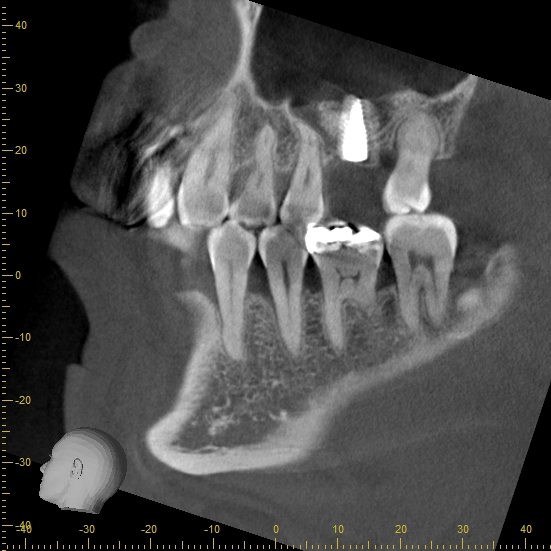

歯がない部分の治療相談で来院された患者様です。 左上奥歯を以前抜歯し、その後義歯を作製したものの違和感があってあまり使用していなかったとのことです。 インプラントも検討したが、骨が少なく難しいと他の歯科医院で言われ義歯を選択したそうです。 レントゲン写真とCTで確認します。 上顎の奥歯の上部には副鼻腔と呼ばれる鼻とつながる空洞が広がっています。 この部分の大きさは元々人によって違うのと、歯を抜いてからの期間が長かったり、歯周病などで状態が悪くなってから抜歯したケースだとこの空洞が広くなり上顎の骨が少なくなっている場合が多くあります。 実際に今回のケースで計測すると上顎には2-3mm程度の骨の厚みしかありません。 インプラントを検討する場合、長さ8mm以上のインプラントで計画を立てることが多いため、骨の厚みが足りない状態です。 短いインプラントを使用するにしても6mmほどの骨の厚みが必要になるため、骨を新たに作らないとインプラントが難しいと考えられます。 この場合、インプラントを諦めて義歯を選択するか、サイナスリフトと呼ばれる外科的に骨を作る処置と併用したインプラントを検討しないといけません。 ”サイナスリフトとは” 上顎の歯を抜いた部分の骨が少ない場合、そのままインプラントをすると上顎洞(副鼻腔)に抜けてしまう可能性があります。 そうならないよう、上顎洞の部分に骨を新たに作り、その部分にインプラントを埋入する方法です。 歯茎を切開、剥離し、骨を露出させます。 骨の部分に一部穴をあけ、上顎洞(副鼻腔)が見えるようにします。 上顎洞内の粘膜を破れないように上に持ち上げます。 粘膜が上に持ち上がったことでできたスペースに人工の骨を填入します。 歯茎を戻します。 骨の厚みが一定量ある場合は、同時にインプラントを入れていきます。 (骨の厚みが極端に少ない場合は、一定期間待機し、人工の骨が自分の骨と同じように置き換わってからインプラントを入れていきます) この状態で6-9ヶ月程度待つとじぶんの骨と同じように置き換わります。 ここまできたら後は被せ物の作製を行なっていきます。 患者様にインプラントを希望される場合、サイナスリフトが必要な旨を説明し、了承を得たため処置に移行しました。 今回は骨の厚みが3mm程度あるため、骨の硬さにも問題がなければサイナスリフトとインプラントを同時に行う方法で計画を立てました。 処置前後で比較します。 インプラントの周りの白い部分が填入した人工の骨です。 インプラントが人工骨に周囲を覆われているのが分かると思います。 処置後は消毒と糸抜きを行い、骨が硬化しインプラントが安定するまで6-8ヶ月程度経過をみていきます。 現在インプラントを扱っている医院は数多くありますが、サイナスリフトなどの骨が少ない時に併用する難易度の高い外科処置に対応していない医院もあります。 アズ歯科桶川院には口腔外科専門医が2名が在籍し、専門性の高い処置を行なっております。 また、インプラント治療が怖い方には麻酔専門医による鎮静下での処置も可能です。 お気軽にご相談ください。 治療期間 9ヶ月 治療費 ¥650,000 + tax インプラント本体+手術料+サイナスリフト 治療のリスク 腫れと痛みが出る可能性がある インプラントが歯周病になる可能性がある